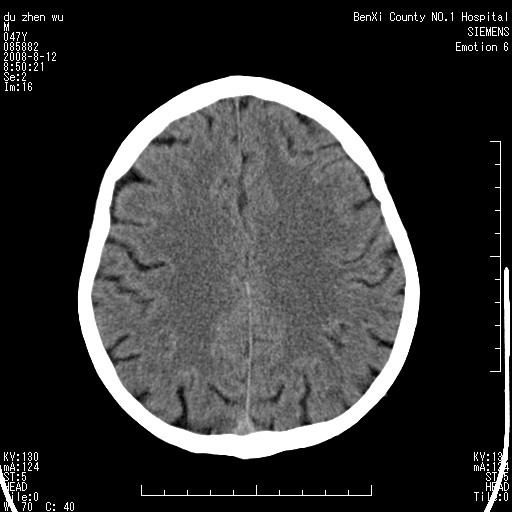

标题: CT15142:M47Y,胼胝体低密度病变 [打印本页]

标题: CT15142:M47Y,胼胝体低密度病变

男、时有神智不清,头晕,能正常回答问题,无肢体偏瘫

考虑胼胝体变性(脱髓鞘病变),找到一篇论文

典型,支持 胼胝体变性(脱髓鞘病变